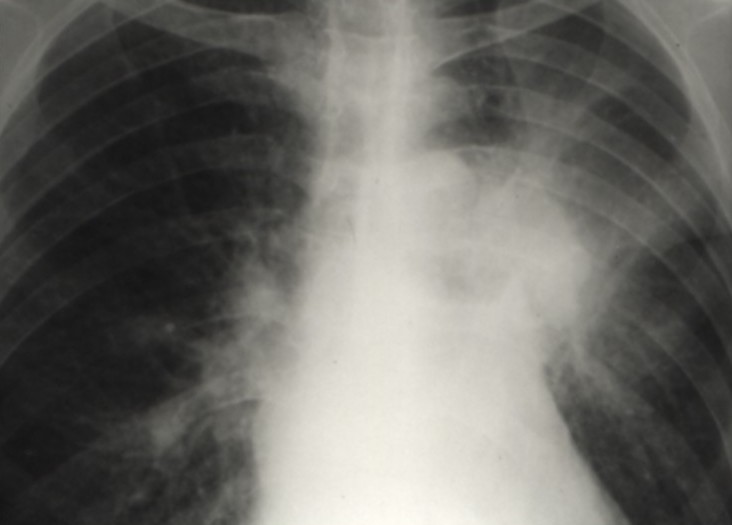

Cancers bronchiques